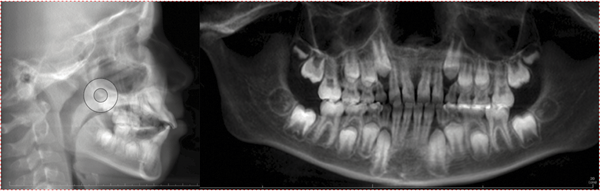

Intraoral examination confirmed an Angle Class I dentofacial pattern with several complex clinical conditions (Figs. 2–3):

• Complete posterior buccal crossbite on the left side; the left maxillary posterior teeth fully overlapped the mandibular buccal segment with no functional contact

• Constricted mandibular arch with the lower left posterior segment lingually tipped and collapsed

• Lower dental midline shifted to the right

• Mild maxillary spacing in the anterior region (U2–2)

• Mild mandibular crowding

• 20% overbite with moderate overjet

Fig. 2: Initial intraoral views (right lateral, anterior, left lateral) demonstrating the complete buccal crossbite on the left side and upper anterior spacing.